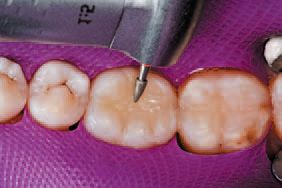

A single increment of Tetric EvoCeram Bulk Fill in shade IVA was then placed in the preparation of tooth No. 30 (Fig. 9), and shaped first with an OptraSculpt® sphere attachment (Fig. 10), then with an OptraSculpt pyramid attachment (Fig. 11). The final anatomy was contoured using a P1 plugger (Fig. 12). As a final step before finishing, the restoration was light cured with the LED curing light (Fig. 13).